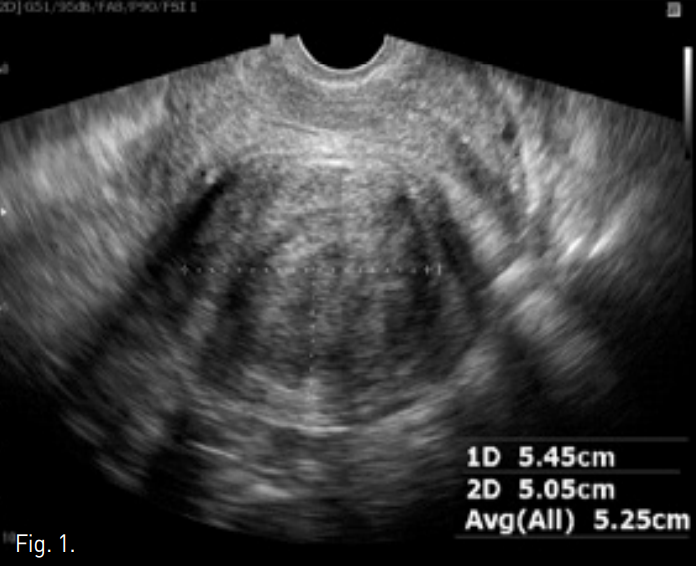

Fig. 2

A-C. T2-weighted transverse (A), coronal (B), and sagi ttal (C) MR images show a huge mass of low signal intensity.

D. T1-weigh ted MR image with contrast enhancement shows a homogeneous enhancing mass.